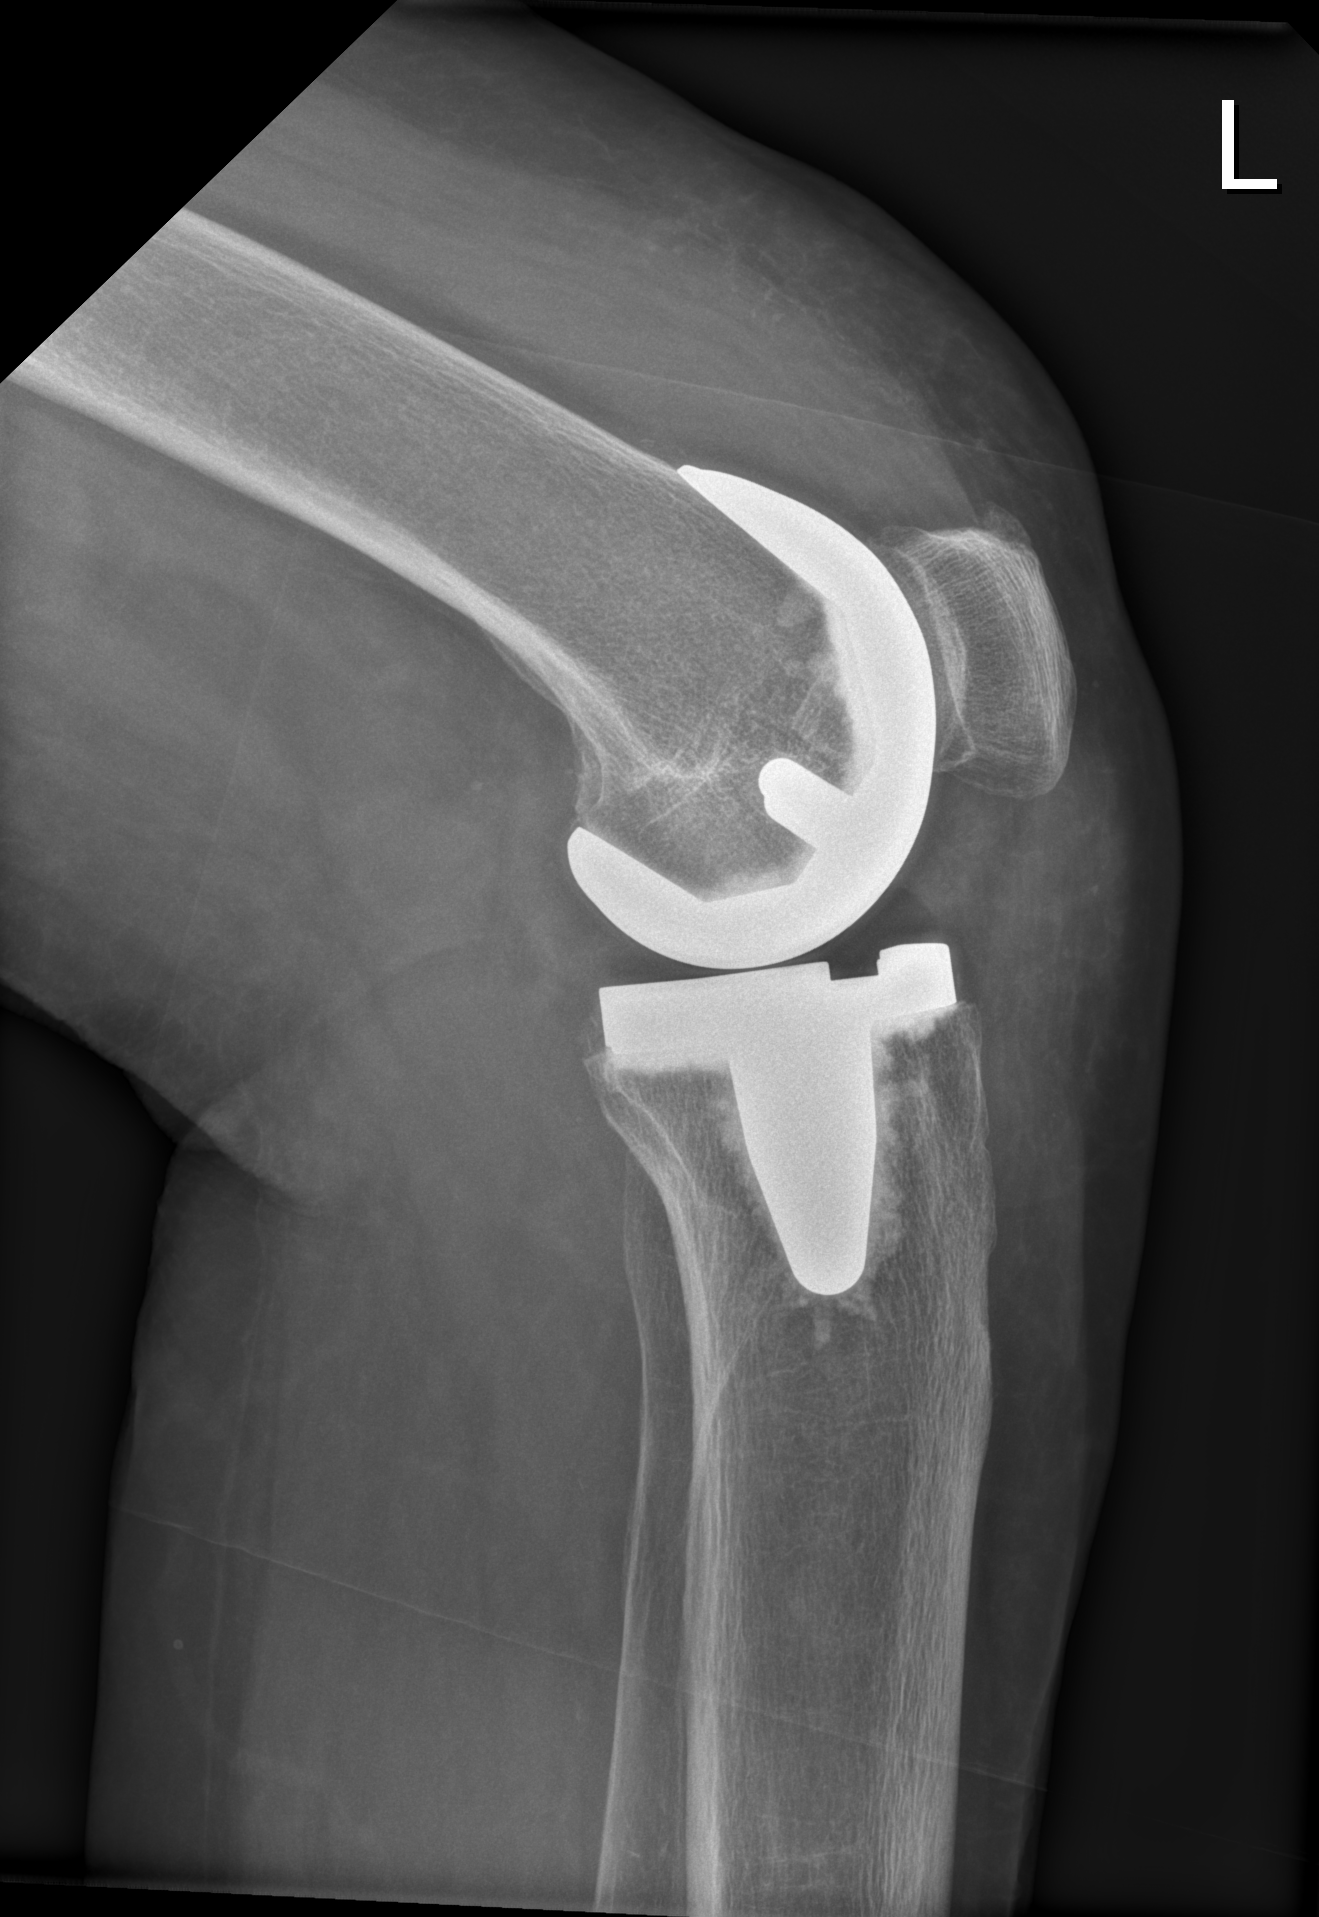

Bei schweren Schäden in mehreren Gelenksteilen ist eine Knie-Totalendoprothese (Knie-TEP) sinnvoll. Dabei werden die Gelenkoberflächen durch Metall ersetzt. Die Kniescheibe muss nur ersetzt werden, wenn diese auch Veränderungen (Knorpelschäden) zeigt.

Knie-Totalendoprothese im Röntgen

Für die Ausrichtung der Endoprothesenteile gibt es im mehrere Möglichkeiten:

- Mechanische Ausrichtung (Englisch: Mechanical alignment knee arthroplasty): Die Ausrichtung erfolgt entsprechend einer geraden Beinachse. Das heißt, dass das Bein nach dieser OP annähernd gerade sein wird, was in den meisten Fällen gut funktioniert, aber nicht immer der natürlichen Bandspannung des Kniegelenks gerecht wird.

- Kinematische Ausrichtung (Englisch: Kinematic alignment knee arthroplasty): Die Ausrichtung folgt der ursprünglichen Stellung der knöchernen Strukturen. Das heißt es wird ein reiner Oberflächenersatz durchgeführt und auf eine gerade Beinachse kein Wert gelegt. Es können zwar Fehlstellungen zurückbleiben, jedoch führt die natürliche Bandspannung im Normalfall zu einer möglichst natürlichen Roll-Gleitbewegung des Kniegelenkes. Dies kann unterstützt werden durch so genannte medial-pivot Inlays. Ein Inlay ist die Plastikeinlage welche zwischen Oberschenkel-Teil (Femur-Komponente) und Schienbein-Teil (Tibia-Komponente). Diese medial-pivot Inlays sorgen für eine möglichst natürliche Knie-Beweglichkeit, da sie die natürliche Form des Schienbeins inklusive Meniskus nachahmen.

- Eine Mischung aus mechanischer und kinematischer Ausrichtung (Restricted kinematic alignment knee arthroplasty), bei der nur ein Teil der Fehlstellung belassen wird. Die genaue Ausrichung wird intraoperativ vom Operateur auf Grund der natürlichen Bandspannung des Patienten entschieden. Dadurch wird ein natürliches Bewegungsmuster des Kniegelenks bei teilweise korrigierter Knieachse erreicht.

In der Nachbehandlung ist die Vollbelastung sofort nach der Operation erlaubt. Krücken werden für die ersten 6 Wochen nach der OP zur Unterstützung empfohlen. Nach einer Knie-Totalendoprothese ist es von großer Wichtigkeit innerhalb der ersten 6 Wochen eine gute Beweglichkeit zu erlangen. Mehrmals tägliche selbstständige Beübung der Beugung und Streckung ist wichtig. Physiotherapie 1-2 mal pro Woche sowie ein Rehab-Aufenthalt (frühestens 6 Wochen nach OP) sind sinnvoll.